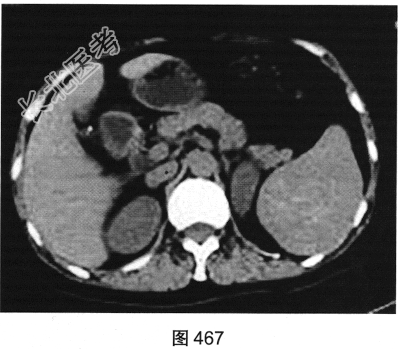

- 多项选择题2.[提示]患者行CT动态增强扫描,如图467~图469所示。对CT图像描述正确的是( )

A、病灶内见条索状钙化灶

B、病灶动脉期无强化

C、CT平扫呈不均匀稍低密度

D、左肾被病灶侵犯

E、病灶门脉期显著强化

F、病灶边界清晰,具有包膜